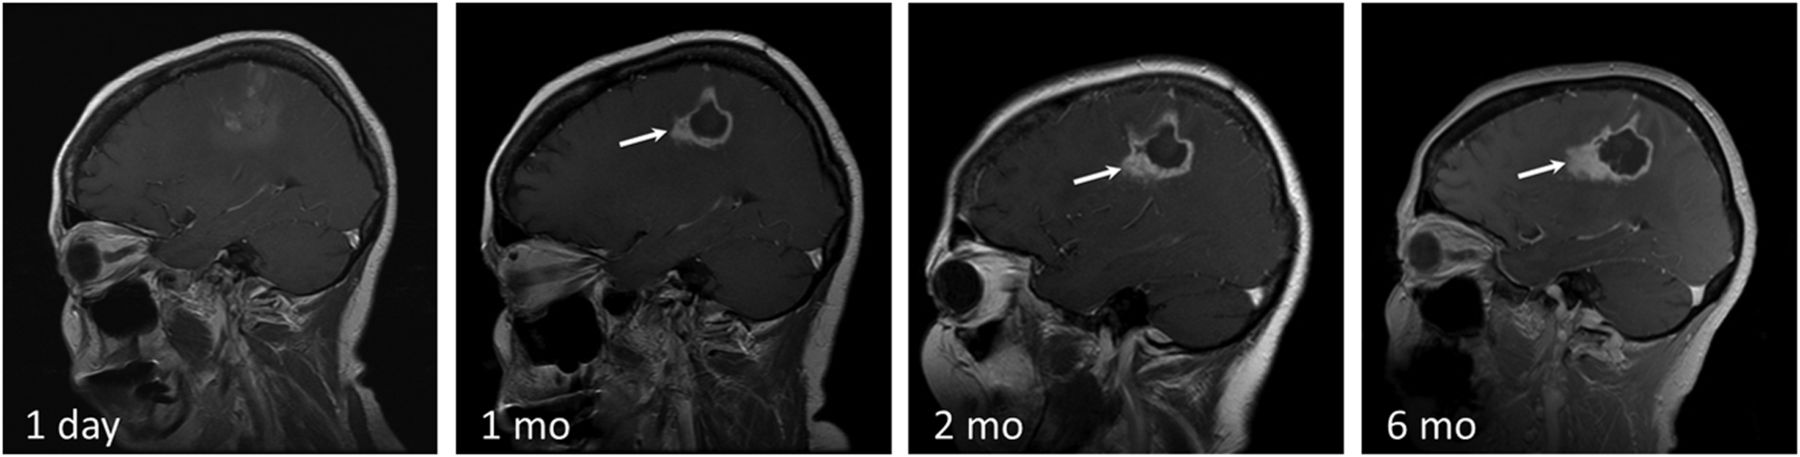

T1 contrast-enhanced images demonstrating the normal evolution of a LITT-treated metastatic left cerebellar lesion, which recurred after SRS in a 70-year-old female patient with history of ovarian adenocarcinoma. Note the expected increase in the size of the treated lesion at 2-month follow-up and a steady decrease in size on subsequent follow-up.

Serial follow-up performed >40 days after the procedure should demonstrate a continuous decrease in the size of the ablated lesion and stable or decreased enhancement (Fig 3). Overall, the entire ablated lesion decreases to 50% of its original size within 93 days of treatment35 and continues to decrease in size for 6–15 months, becoming more homogeneous in appearance. Peripheral enhancement that persists or gradually decreases in size is a sign of the normal evolution of the ablated lesion. Any interval increase in lesion size, heterogeneity, peripheral nodular enhancement, restricted diffusion, CBF/CBV, and surrounding edema in a lesion treated >40–60 days prior should raise suspicion for recurrence (Fig 5).36,37 Recurrence usually occurs within the peripheral rim of enhancement and presents as new or enlarging peripheral enhancing nodularity (Figs 5) or simply as thickening of the rim of enhancement (Fig 6). Comparison with prior images is vital in monitoring tumor recurrence because normally evolving lesions can demonstrate asymmetric enhancement similar to that of recurring lesions. Therefore, irregularly enhancing lesions require close-interval follow-up. Any increase in size, enhancement, or surrounding edema should be further assessed with adjunctive techniques such as MR spectroscopy, perfusion imaging, or PET.

Disease recurrence after treatment with LITT. T1 contrast-enhanced images in a 58-year-old man with GBM status post surgical excision, chemoradiation, and SRS for a recurrent left parietal lobe lesion. The second recurrence was treated with LITT. Note irregular peripheral nodular enhancement at 1-month follow-up (white arrow), which progressively increases in size at 2 and 6 months. Findings are consistent with disease recurrence.